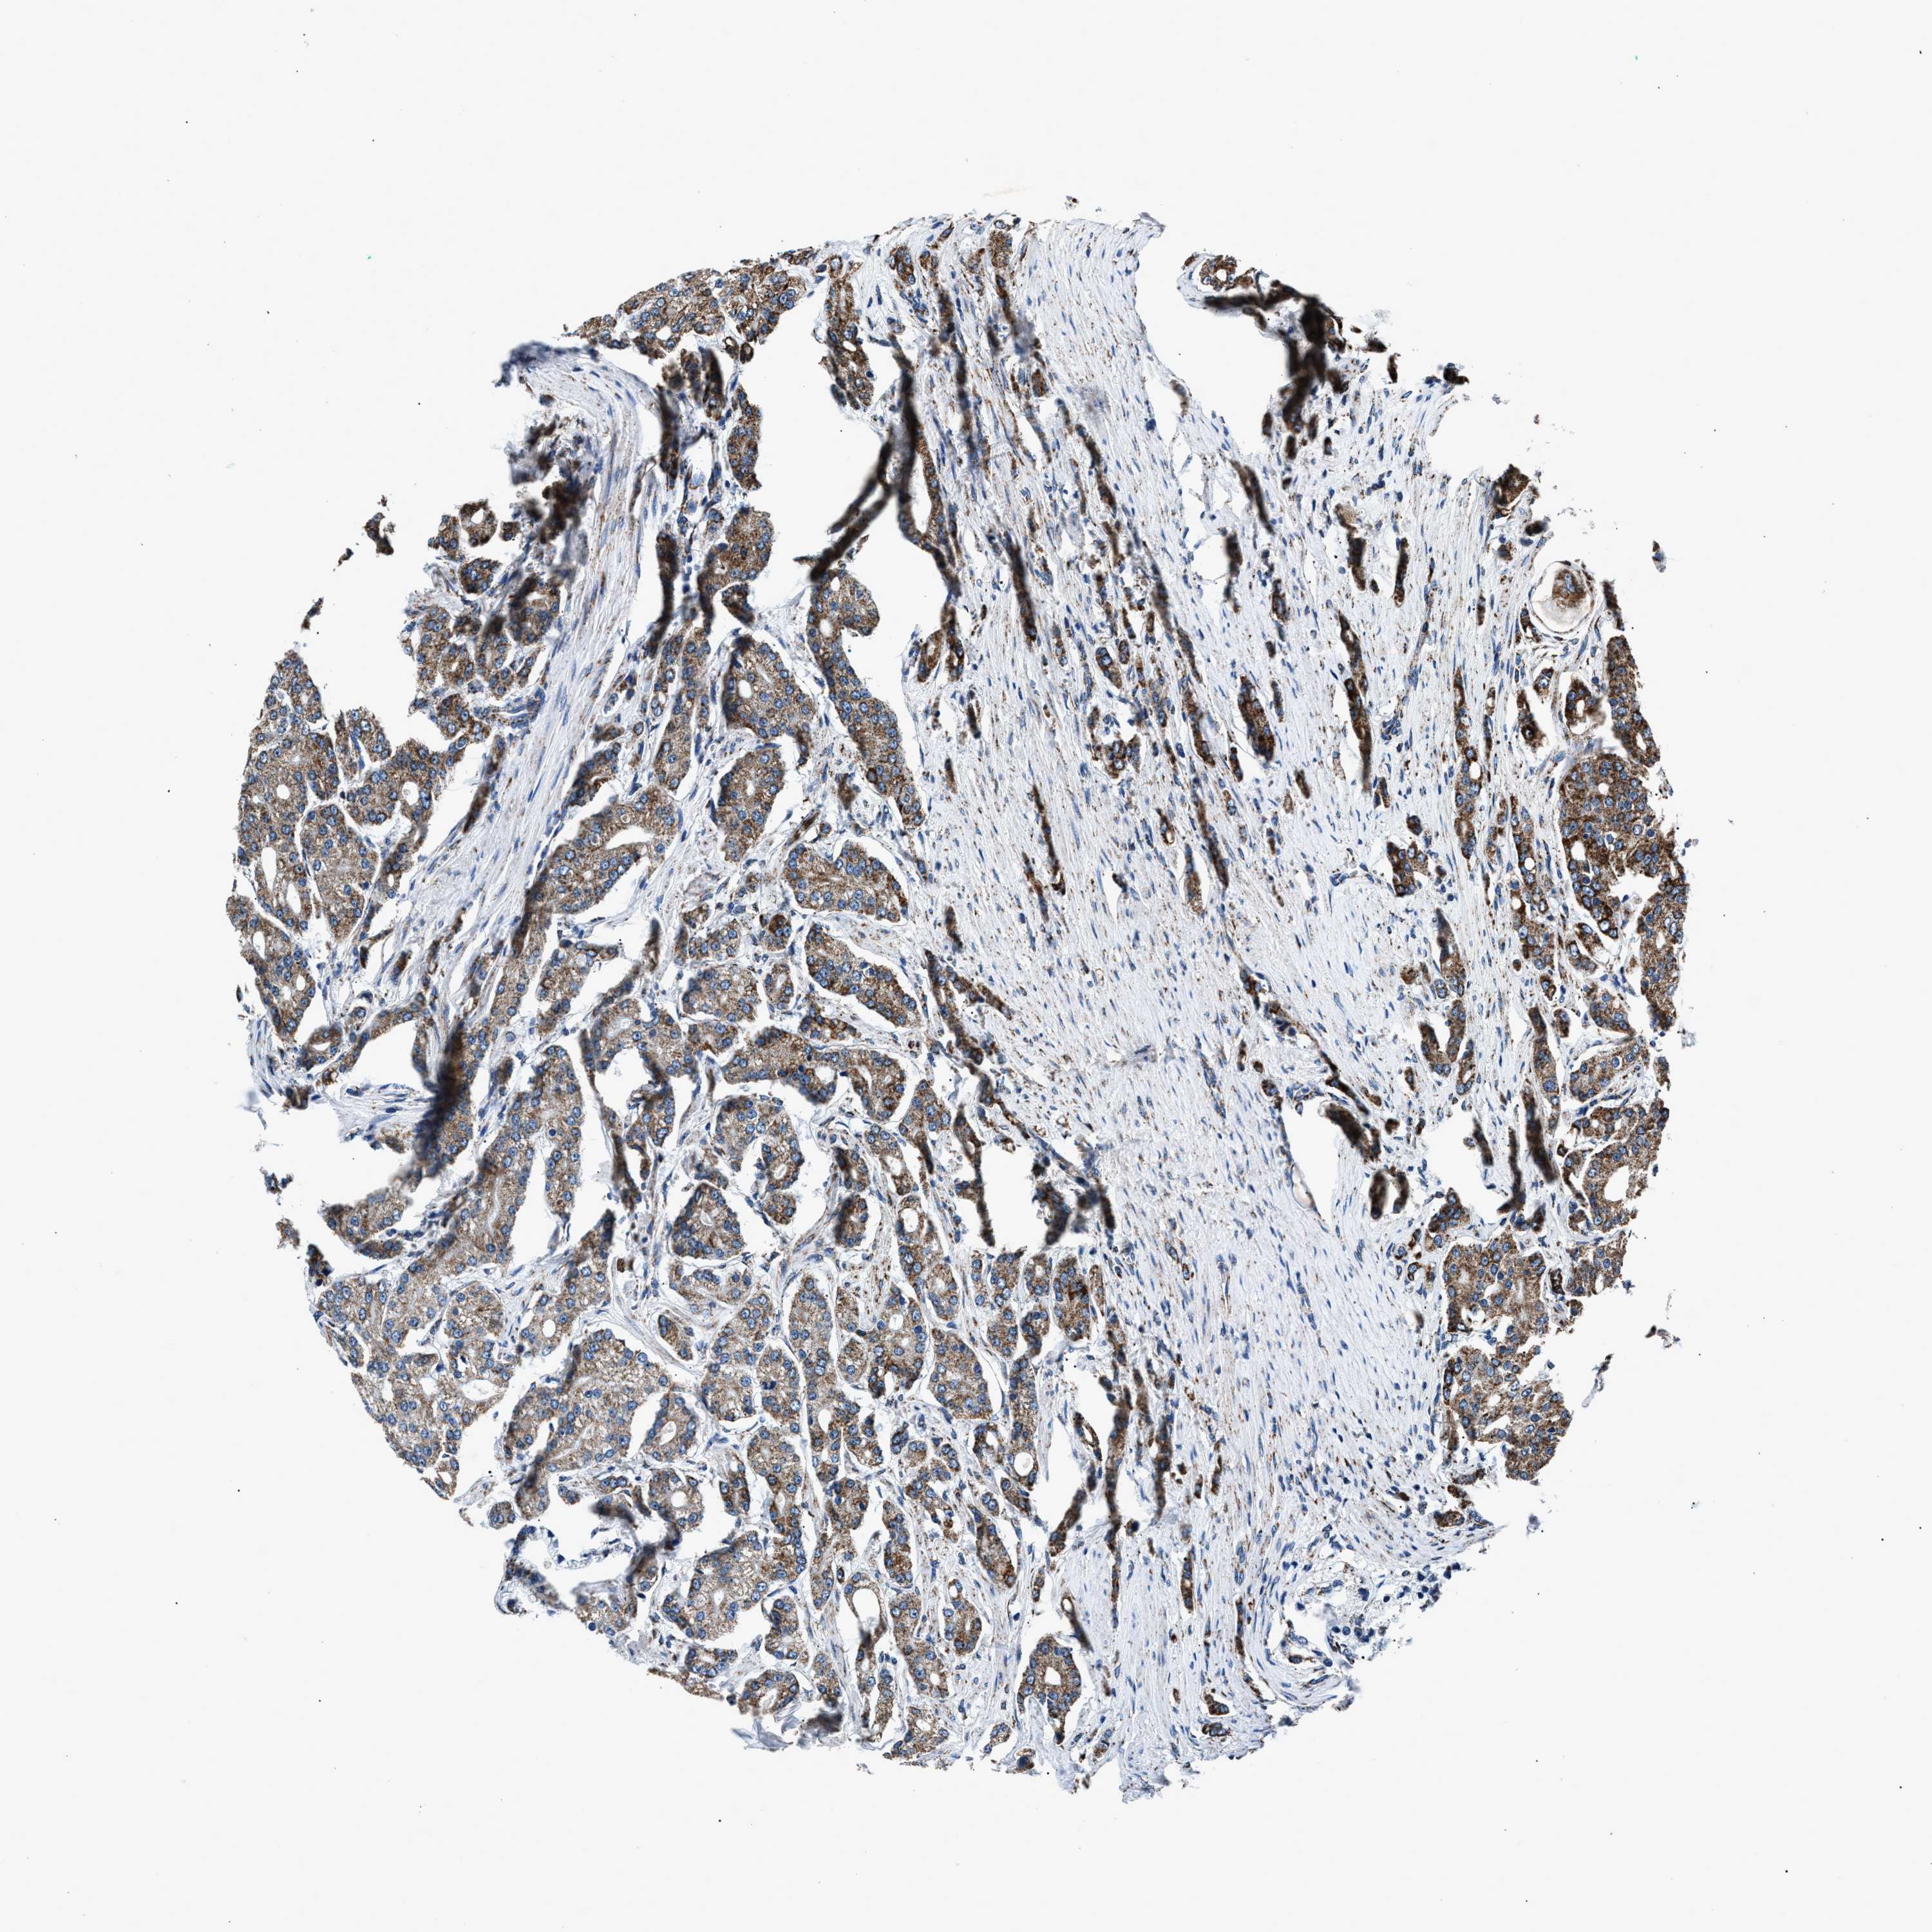

PROSTATE CANCER - Protein expressioni

A mouse-over function shows sample information and annotation data. Click on an image to view it in a full screen mode. Samples can be filtered based on level of antibody staining by selecting one or several of the following categories: high, medium, low and not detected. The assay and annotation is described here.

Antibody stainingi

Antibody staining in the annotated cell types in the current human tissue is reported as not detected, low, medium, or high, based on conventional immunohistochemistry profiling in selected tissues. This score is based on the combination of the staining intensity and fraction of stained cells.

Each image is clickable and will lead to virtual microscopy that enables deeper exploration of all samples and also displays staining intensity scores, fraction scores and subcellular localization as well as patient and tissue information for each sample.

Antibody HPA019522

Antibody HPA021002

Staining

High

Medium

Low

Not detected

Intensity

Strong

Moderate

Weak

Negative

Quantity

>75%

75%-25%

<25%

None

Location

Nuclear

Cytoplasmic/membranous

Cytoplasmic/membranous,nuclear

Adenocarcinoma, High grade

Adenocarcinoma, Low grade